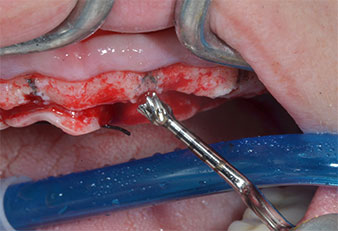

Insert Piezomed I2A/I2P

Fig. 4 : L’étape suivante est l'agrandissement pilote à l'aide des inserts Piezomed I2A/I2P, qui sont utilisés selon un mouvement horizontal rotatif.